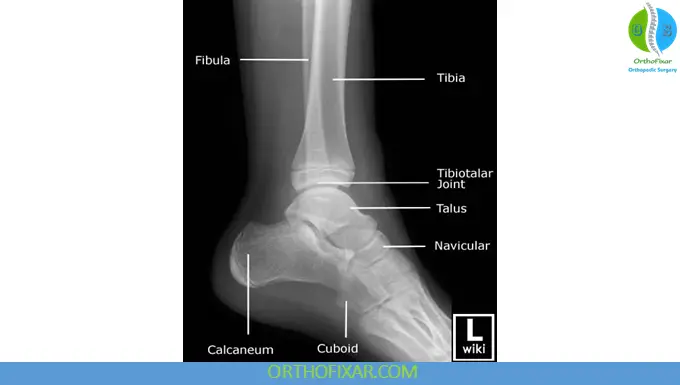

2. Lateral View of the Ankle

The lateral view provides a side profile of the ankle joint, showing:

- Tibia, fibula, talus, and calcaneus

- Posterior malleolus and subtalar joint

This projection is critical in evaluating X-ray of a fractured ankle, especially posterior malleolar fractures and joint effusion. The examiner must note whether the epiphyseal lines are normal and whether there is any increase or decrease in joint space. When viewing lateral films, the examiner must also be aware of Sever’s disease and Köhler’s disease. The presence of a Haglund deformity (abnormally enlarged posterosuperior aspect of calcaneus)